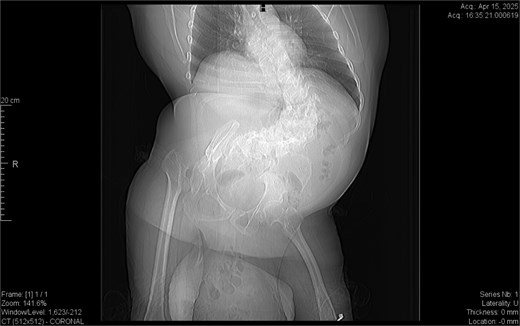

CT imaging (Figs 2–5) revealed a right inguinal hernia containing small bowel loops, ascending colon, the second and third portions of the duodenum, and the pancreatic head. The pancreatic head appeared rotated and displaced inferiorly into the hernia sac, without signs of acute pancreatitis.

Horizontal CT view inguinal hernial sac with pancreatic head and D2 and D3 segment of duodenum.

Coronal CT view visualization of vascularization of pancreatic head after i.v. contrast.